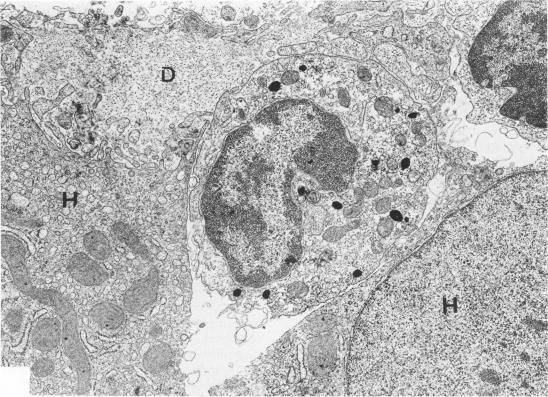

In an attempt to characterize in vivo the immune cells cytotoxic to hepatocytes in patients with chronic active hepatitis (CAH), a quantitative ultrastructural analysis of leukocytes in close contact with hepatocytes was performed in 13 patients with untreated HBsAg-negative CAH. Mononuclear phagocytes were identified by detection of endogenous peroxidase. Of the leukocytes, 8.3-4.1% were mononuclear phagocytes, 12.5-25.8% were large lymphocytes with a prominent secretory apparatus, assumed to represent mostly killer cells (T-cytotoxic cells and/or null cells), 12.2-56.8% were small lymphocytes poor in cytoplasmic organelles, and 0-45.8% were plasma cells. Patients with high serum transaminase levels had significantly more mononuclear phagocytes (P less than 0.001) and significantly fewer plasma cells (P less than 0.001) and small lymphocytes (P less than 0.001) than patients with lower disease activity. The profile of the leukocytes in contact with hepatocytes in these CAH patients suggests that mononuclear phagocyte-mediated mechanisms play an important role in hepatocyte necrosis in vivo.

为了在体内鉴定慢性活动性肝炎(CAH)患者中对肝细胞具有细胞毒性的免疫细胞,对13例未经治疗的HBsAg阴性CAH患者中与肝细胞紧密接触的白细胞进行了定量超微结构分析。通过检测内源性过氧化物酶来识别单核吞噬细胞。在白细胞中,8.3 - 4.1%是单核吞噬细胞,12.5 - 25.8%是具有突出分泌装置的大淋巴细胞,推测主要代表杀伤细胞(T细胞毒性细胞和/或裸细胞),12.2 - 56.8%是细胞质细胞器较少的小淋巴细胞,0 - 45.8%是浆细胞。血清转氨酶水平高的患者比疾病活动度较低的患者具有明显更多的单核吞噬细胞(P < 0.001),明显更少的浆细胞(P < 0.001)和小淋巴细胞(P < 0.001)。这些CAH患者中与肝细胞接触的白细胞谱表明,单核吞噬细胞介导的机制在体内肝细胞坏死中起重要作用。